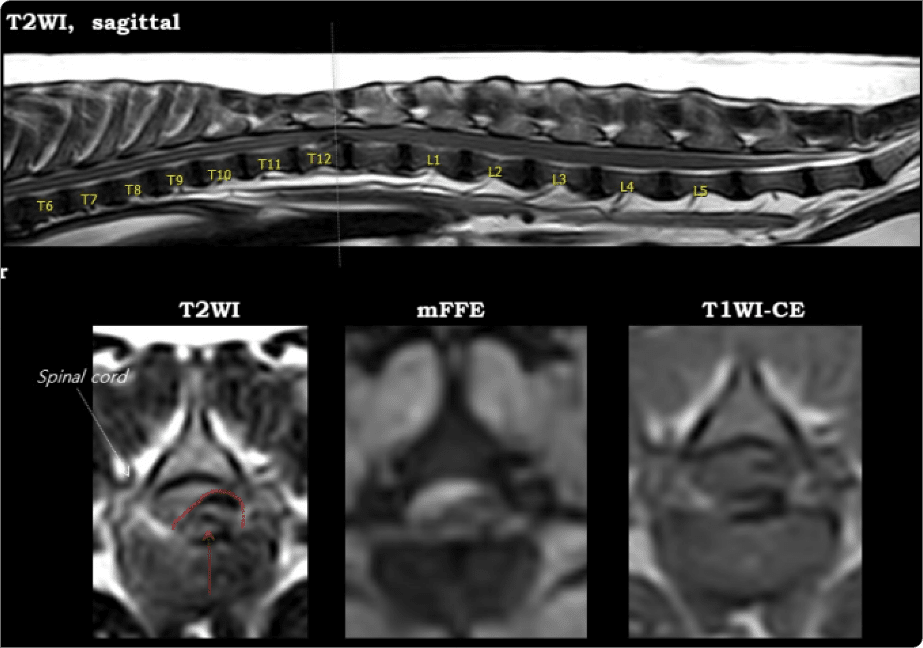

디스크로 잘 알려진 질환으로, 추간판이 돌출해 척수 신경을 압박.

경추·흉추·요추에서 발생하며 위치에 따라 증상과 수술 방법이

달라지며 정확한 진단과 MRI 검사가 필수적입니다.